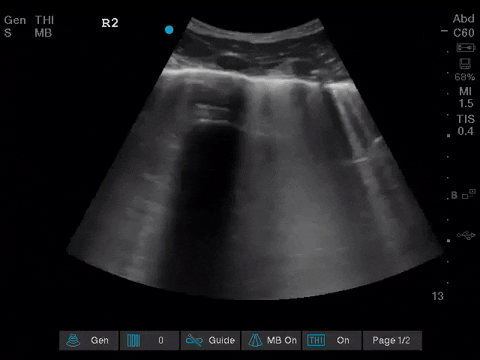

The POCUS team was asked to specifically to assess her lungs to help determine the cause of her dramatically increased oxygen requirements.

Before giving their clinical interpretation of the LUS findings, the POCUS team also scanned the heart and vasculature to obtain a more complete picture.

1. When scanning the lungs, a comprehensive, bilateral lung scan is far superior to a single clip; as this will offer more information and permit an interpretation based on the overall pattern of findings. Had this patient only had the R1 area scanned, for example, we may have reached the erroneous conclusion that her hypoxemia was likely due to pulmonary edema.